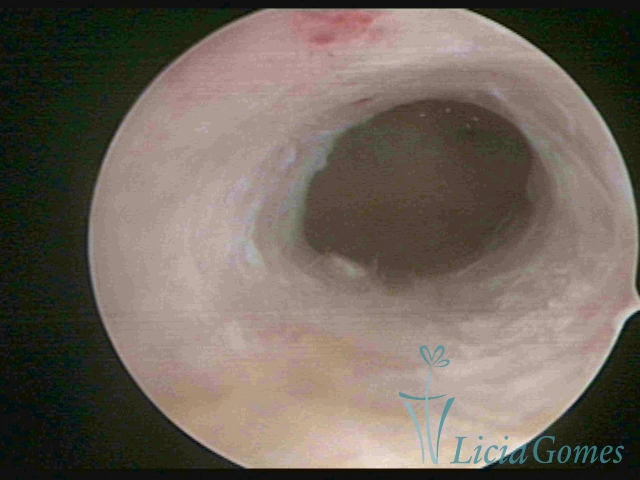

Third part or upper section

Presents the mucosa with a smooth, poorly vascularized surface, to the internal orifice